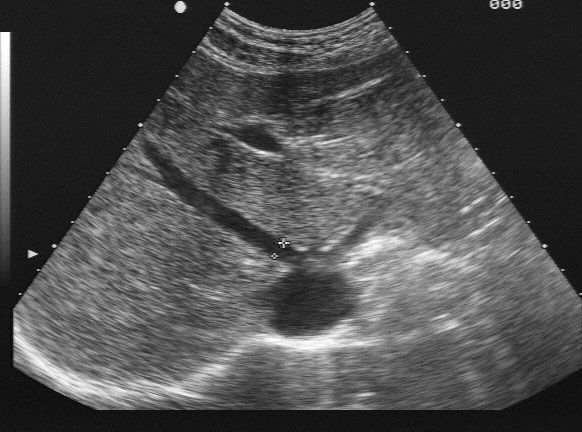

Hepatologie

Für Patienten mit Lebererkrankungen bieten wir eine Spezialsprechstunde an. Neben einer ausführlichen Diagnostik (incl. Leberbiopsie, wenn notwendig) wird eine Therapie und Überwachung von Patienten mit folgenden Erkrankungen angeboten:

• Langzeitbetreuung von Patienten mit Leberzirrhose jeder Genese (HCC-Vorsorge)